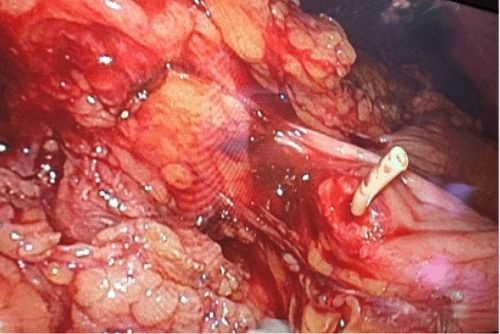

A two-stage procedure was performed on the patient for VP shunt revision. The first stage involved externalizing the proximal end of the shunt at the right chest wall. Laparoscopic access was then obtained through ports placed in the right and left anterior axillary lines, as well as the left and right periumbilical regions. Upon visualization, significant inflammation and dense adhesions were found around the VP shunt's entry point into the peritoneal cavity. These adhesions were taken down to allow for exposure of the shunt entrance. The intra-abdominal portion of the shunt was then divided, with the proximal segment pulled back into the abdomen. Further exploration revealed the VP shunt entering the transverse colon, as documented in Figure 4. Subsequently, the extracolonic portion of the shunt was divided and removed. This resulted in a clean-based 1 cm hole in the transverse colon with good vascularity. The colotomy was then laparoscopically closed in a figure-of-eight pattern using 3-0 Vicryl suture. To reinforce the repair, a modified Graham patch was created using omentum secured with 3-0 silk sutures over the closed colotomy site. Finally, a 19 French Blake drain was placed and secured over the transverse colon before being externalized through the left lateral port site.

Figure 4. Laparoscopic View Showing Protrusion of VP Shunt Through Transverse Colon. Published with Permission

In this case, the decision for surgery was based on physical examination and CT findings indicating inflammation at the perforation site. Laparoscopy was chosen initially to visualize the perforation. Knuth et al. (2013) reported a similar case successfully managed with laparoscopic surgery, utilizing an Endo-GIA stapler to resect the perforation area.21 Given the size and clean-based nature of our patient's colotomy, resection was deemed unnecessary. An intraoperative drain was placed near the colotomy repair. The patient recovered well, and the drain was removed without evidence of leakage.